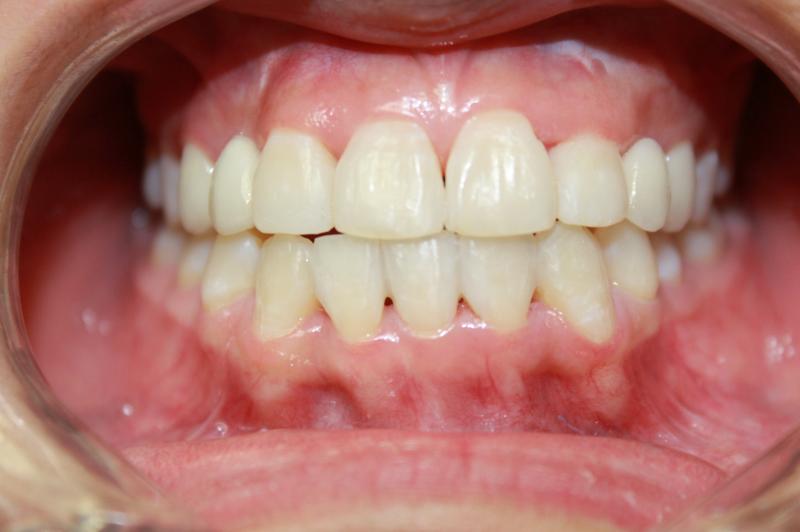

INVISALIGN - 13 months, 1 lower tooth removal, 1 series of aligners to align teeth and create the proper amount of space for 2 cantilever bridge to replace congenitally missing cuspids. COSMETIC DENTISTRY - 2 porcelain cantilever bridges and cosmetic bonding to reshape incisors and close gingival spaces. TOTAL TREATMENT TIME, 15 months

Cosmetic Dentistry, Mid-line Asymetry, Missing Teeth, Severe Crowding